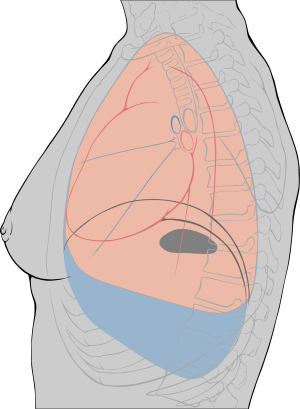

الانصباب الجنبي

تحدث بعض حالات التهاب الجنبة بسبب وجود كميات زائدة من السائل الذي يتراكم في الجوف الجنبي. يطلق على هذه الحالة اسم الانصباب الجنبي. عادة ما يرغم تراكم السائل الطبقتين الجنبيتين على الانفصال لذلك لا تحتك الطبقتان ببعضهما البعض أثناء التنفس. ويؤدي ذلك إلى تخفيف ألم التهاب الجنبة. من الممكن لكمية كبيرة من السائل الزائد أن تدفع الجنبة باتجاه الرئة أو جزء من الرئة مما يؤدي إلى انهيارها. وقد يؤدي ذلك إلى صعوبة في التنفس.

في بعض حالات الانصباب الجنبي يحتوي السائل على عدوى مما يؤدي إلى تحوله إلى خراج. يطلق على هذه الحالة اسم دُبَيلَة.